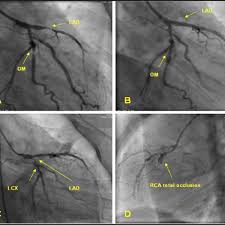

انظروا الى التضيقات بالشرايين التاجيه في القسطره القلبيه بحيث انها بحد ذاتها تحتاج علاج

وبالتالي

احتشاء عضلة القلب myocardial infarction

واخيرا الصدمه الوعائيه القلبيه cardiogenic shock